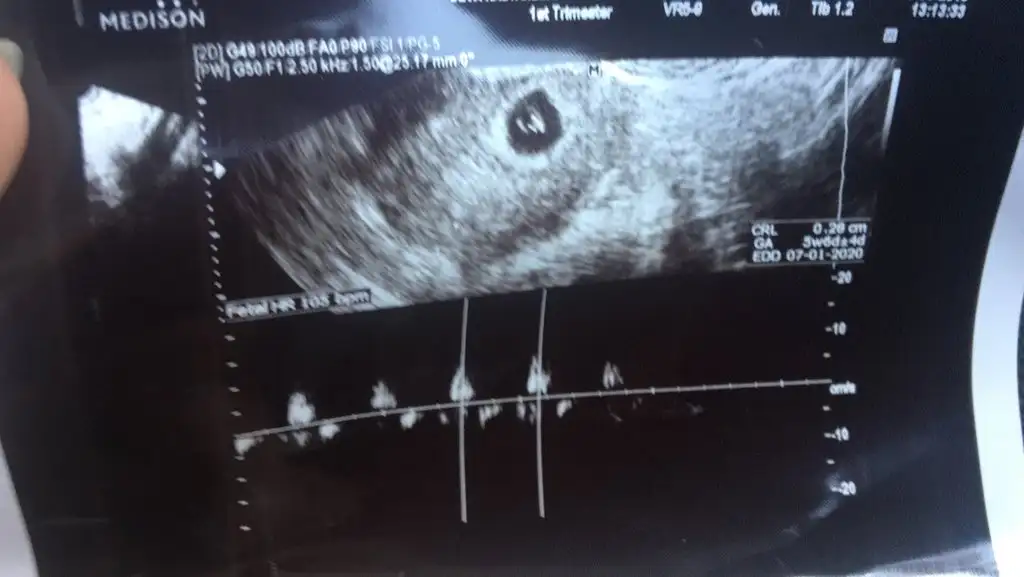

Kızlar ben de 10. Haftamdayım bana da tahminde bulunabilir misiniz